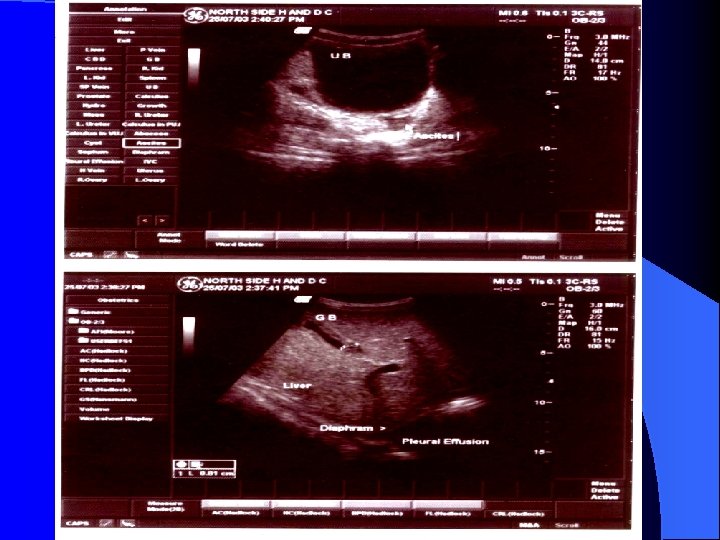

l WHO Diagnosis D. H. F Criteria For DHF : l Fever, Minor or Major Hemorrhagic manifestations. l Thrombocytopenia ( < 100000 / mn 3) l Objective evidence of increased capillary permeability (hematocrit increased > 20%) Xray pleural effusion l Hypoalbuminemia. l DSS : Above mentioned criteria plus hypo tension and narrow pulse pressure ( < 20 mm of Hg)

Management Indications of hospitalizations § l l l l l Restlessness or lethargy frequent vomiting one or two days of febrile illness. Cold extremities or circumoral cyanosis. Bleeding in any form. Rapid and weak pulse. Capillary refill time > 3 seconds. Narrowing of pulse pressure (<20 mm Hg) or Hypo tension. Hematocrit of 40 or rising hematocrit. Platelet count of < 1, 00000/ mm 3 Acute abdominal pain Evidence of Plasma leakage. Eg. Pleural effusion /Ascities

Polyserosities l Need the insertion of intercostal tube or ascitic drainage respectively. l Caution must be taken before drainage as the chances of sever hemorrhages are high. l Patients should be haematologically stabilized first with use of fresh whole blood, FFP or platelet concentrates and drainage of these fluids should be done slowly to prevent sudden circulatory collapse.

Polyserosities Large pleural effusions during the recovery phase after 48 hours may need small doses of frusemide (0. 25 to 0. 5 mg / kg B/w 6 th hourly) with these method it may possible to avoid insertion of intercostal drains. l Generally steroids do not shorten the duration of disease or improve the prognosis in children receiving careful supportive therapy. l